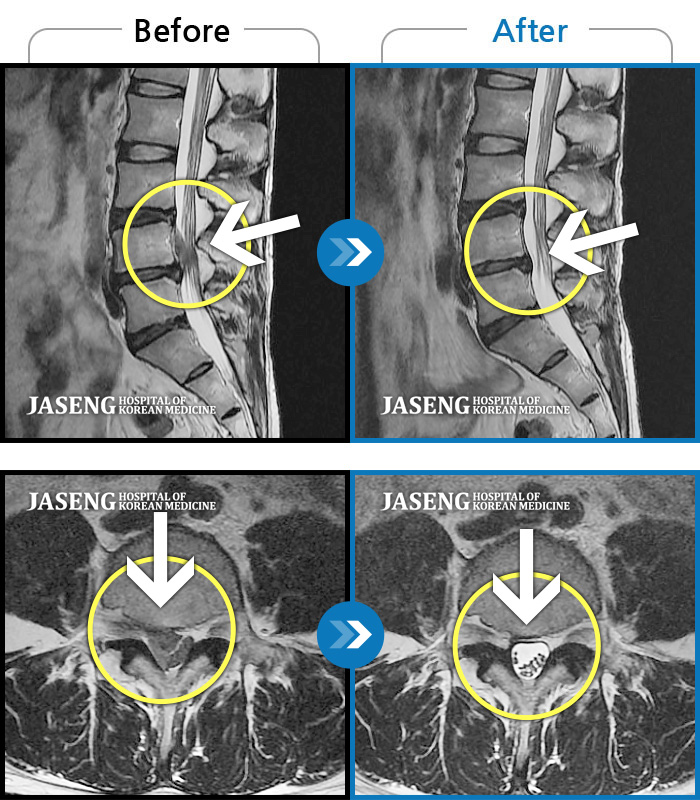

ȯںп Ǹ ǿ ԿǾ, ο ġ ۿ Ƿ ġḦ Ͻñ ٶϴ.